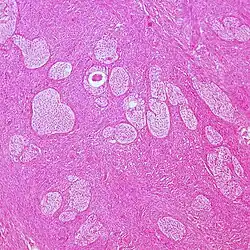

| Surface epithelial-stromal tumor | Serous tumor | 25% | 18.5% | Benign serous tumors of the right ovarian cyst are thinwalled unilocular cysts that are lined by ciliated pseudostratified cuboidal or columnar epithelium.[9] |

|

| Mucinous tumor | 15% | 8.8% | Benign mucinous tumors of the ovary consist of simple, nonstratified columnar epithelium with basally-located hyperchromatic nuclei and resemble gastric foveolar epithelium.[9] |

| |

| Endometrioid tumor | 1% | Almost 100% | Tubular glands, resembling endometrium.[10] |

| Other surface-epithelial tumors | 1.5% | Others include mainly malignant mixed Müllerian tumor, Brenner tumor and mixed epithelial tumor.[5] | ![]() | ||